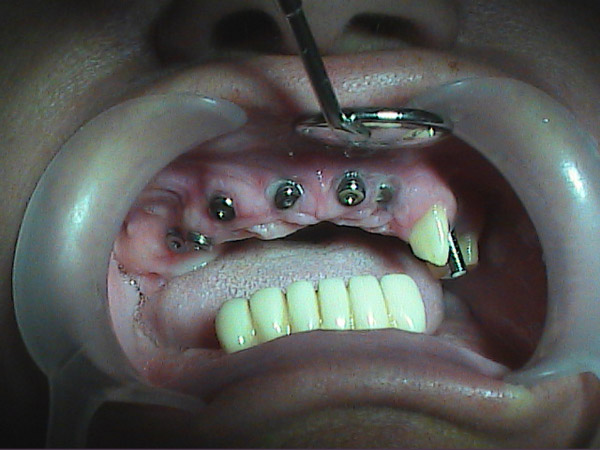

Case Studies - Dental Implants

Here you can view some of our dental implants case studies.